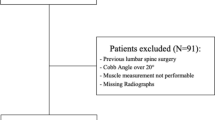

Six patients scheduled for a single-level degenerative lumbar disc disease by traditional (open) lumbar decompression laminectomy technique [22] at the L4–L5 or L5–S1 discs as well as ten healthy volunteers with no recent back complications were volunteered to undergo MR scans twice within an interval of about 6–7 months (Table 1). For patients, the initial MR scans were taken the day before operation. After routine physical and neurological tests, all patients were diagnosed with persistent low back pain as well as weakness and radiculopathy in the lower extremity (loss of motor power) caused by degenerative disc disease (herniated disc) as determined on MR images. All patients were operated on at a single institution by the same surgeon with more than 15 years of experience. The surgeon was not aware of the nature of this study so made no particular attempt to minimize muscle injuries. The subjects were positioned prone while skin incisions were made vertically along the center line. Paraspinal muscles were dissected and detached from the spinous process and lamina to make lamina visible (wound depth from skin to lamina). Bilateral decompression via vertebral lamina fenestration was accomplished with the muscles being pulled using a spinal retractor. After laminectomy, partial discectomy was performed by excision of herniated disc tissues. Each surgery lasted ~120 min with the muscle retraction time of ~100 min. Status of facet joints were normal and no denervation of these joints occurred. Patients were mobilized and were walking the day after surgery and no specific rehabilitation exercises were followed. The study was approved by the ethics committee and informed consent was read and signed by all subjects.